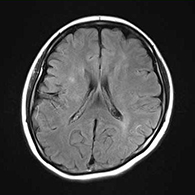

<画像所見>

左眼の奥に大きな動脈瘤認める。

(→動脈瘤)